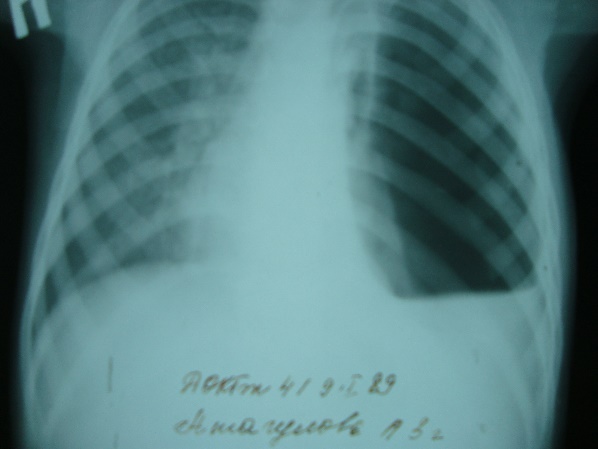

Какой патологический процесс в легких вы видите// пневмония левого легкого// пневмоторакс слева// +гидропневмоторакс слева// плеврит слева// рак левого легкого